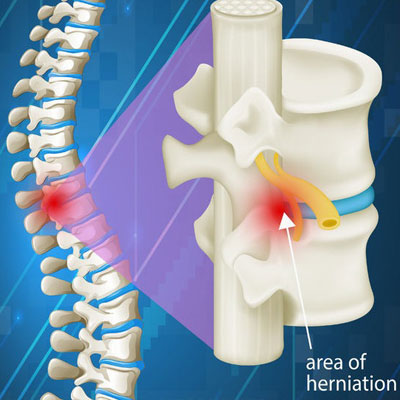

Diseases Treated

Spinal Problems Digestion Diseases Joints & Bones Problems Neurological Diseases Cardiovascular Disorders Respiratory Diseases Thyroid Problems Skin Diseases Diabetes Kidney Problems Male Reproductive Diseases Gyanecological Problems Opthalmic (Eyes) Problems Auto Immune Diseases Children Problems Hair Problems Addiction Rehabilation of Accidential Cases